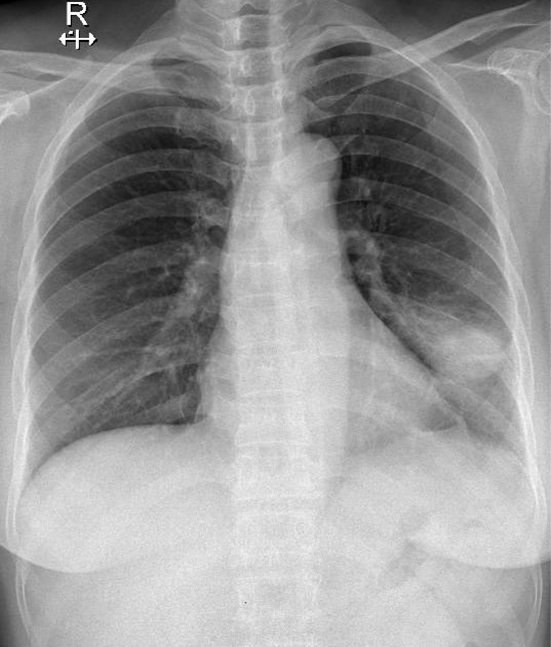

Hãy phân tích tình huống NỮ 58 tuổi

1-U thùy dưới phổi (T) kèm viêm phổi xung quanh